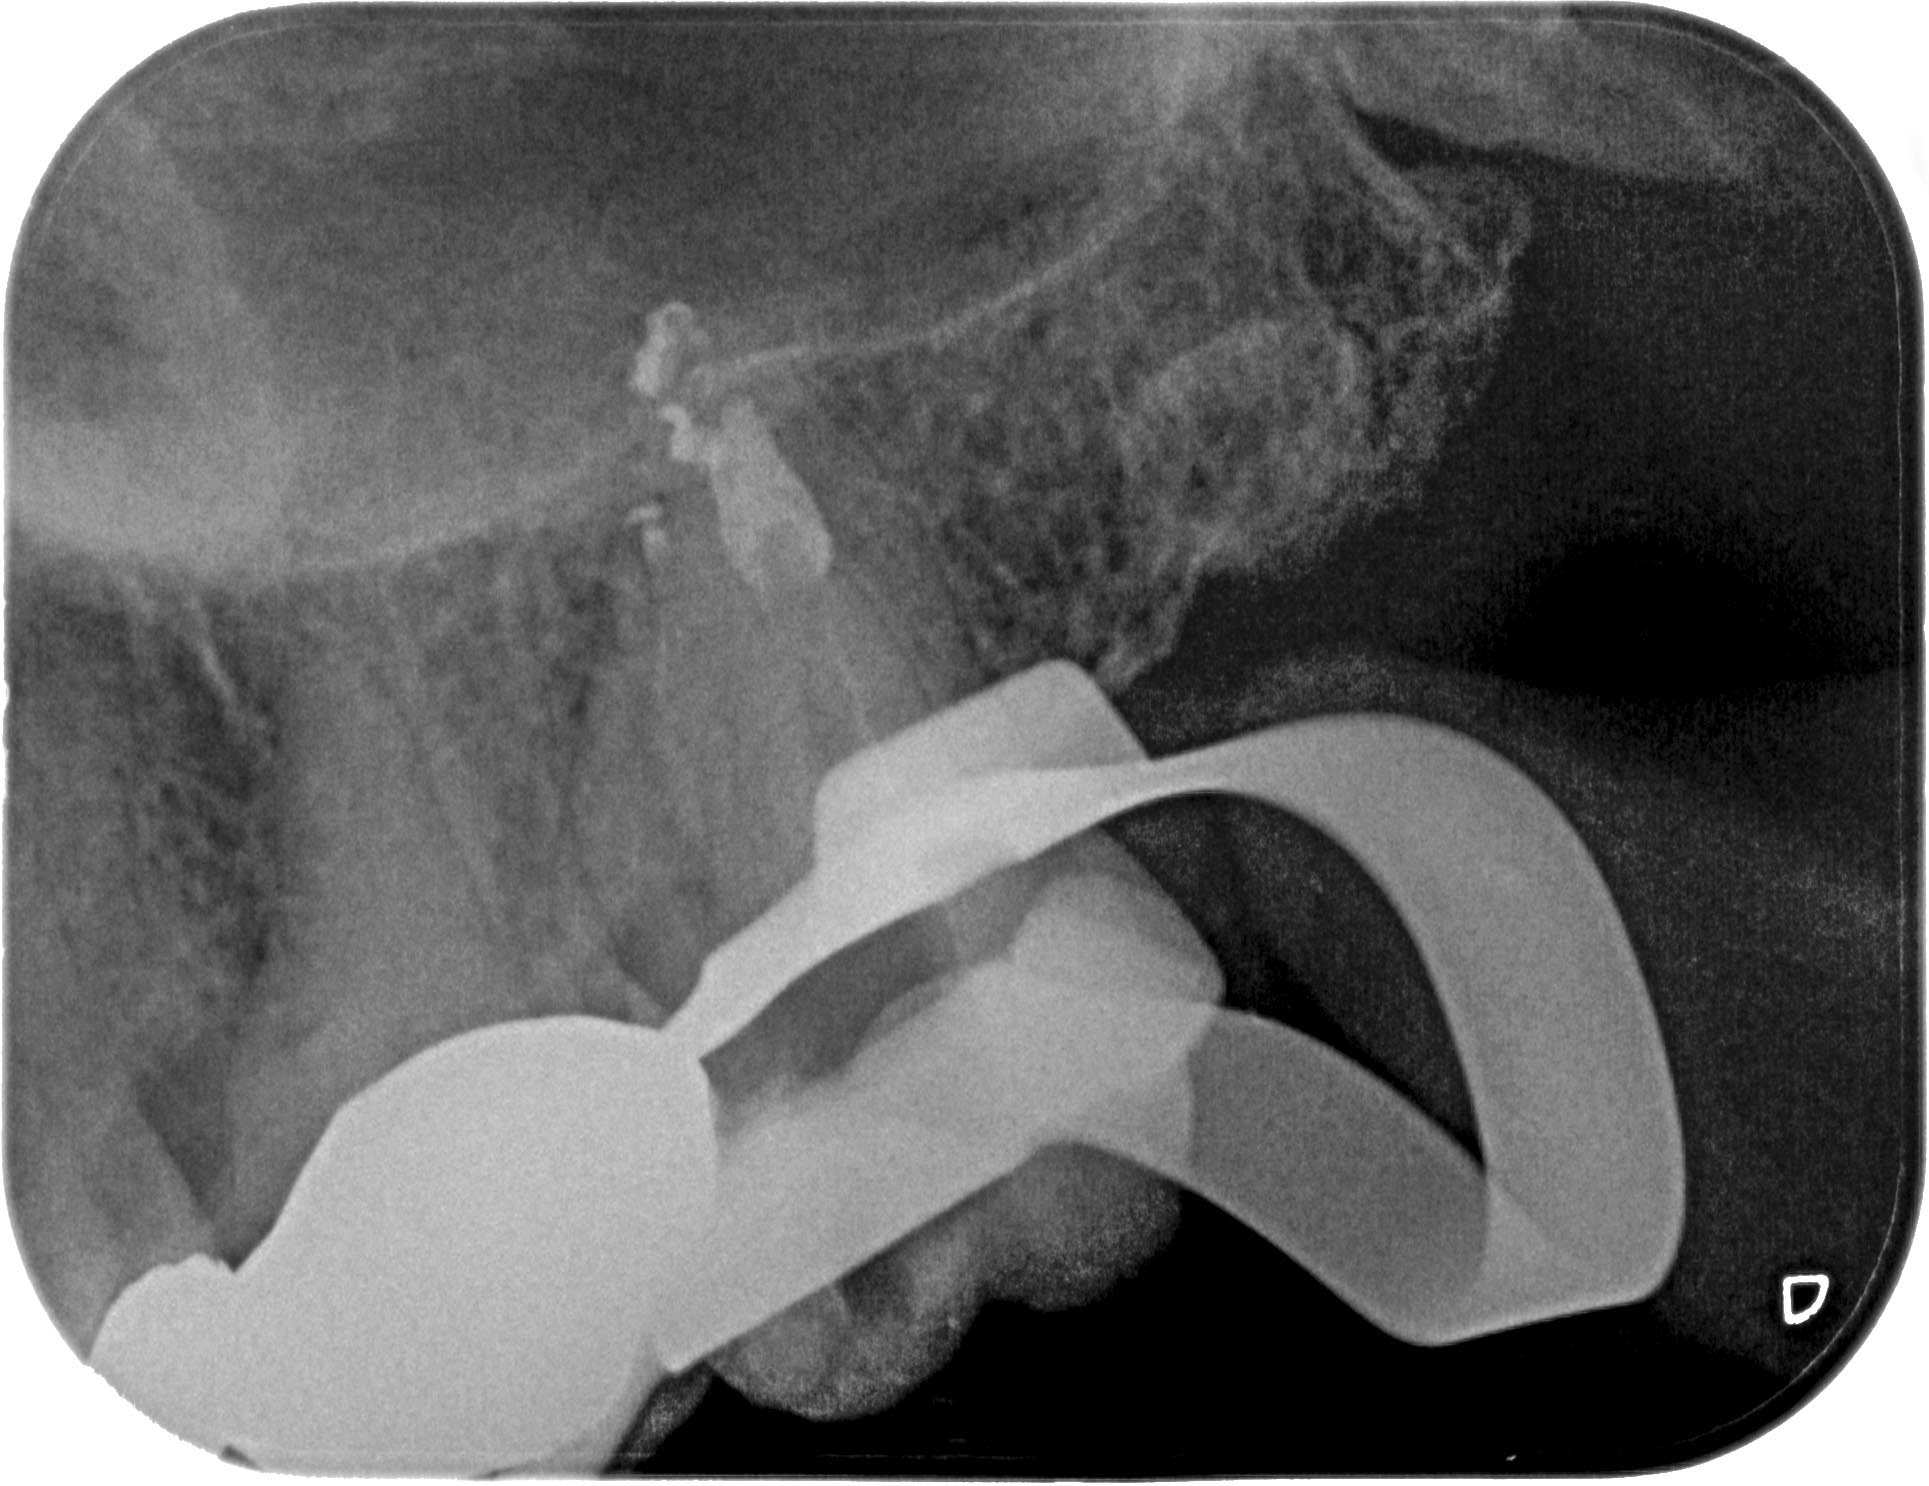

KC27-1-4 Veröffentlicht 25. Juni 2015 am 1929 × 1486 in Zahn 27- Interne Resorption, apikale Aufhellung